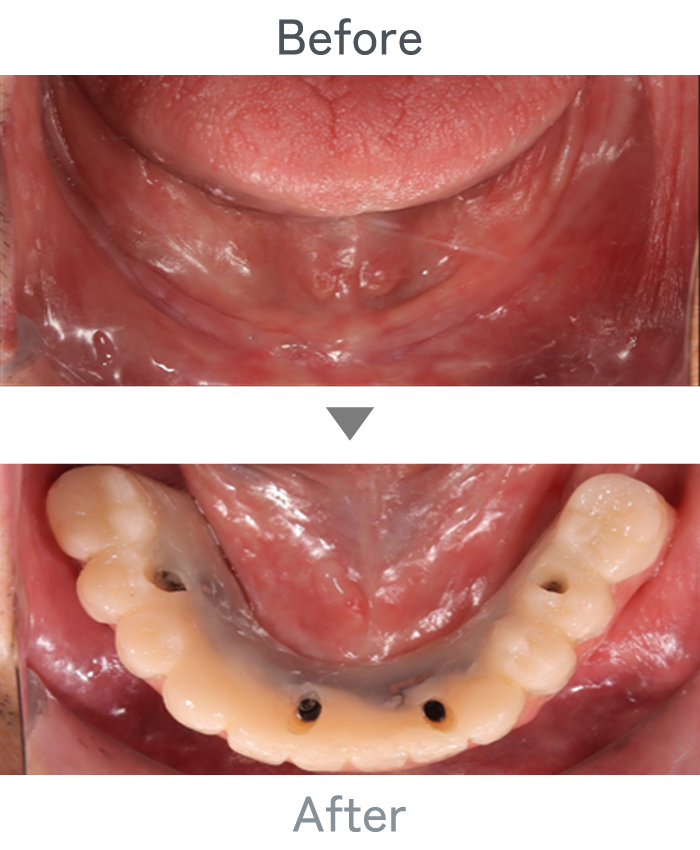

All-on-4

+

金属床義歯

主訴 入れ歯が使えなくて固定式にしたい

治療法 上顎:金属床義歯

下顎:All-on-4

治療期間 4ヶ月

※仮歯は手術当日に装着

費用 ・上顎金属床義歯:200,000円

・下顎All-on-4:2,500,000円

小 計:2,700,000円

消費税:270,000円

合 計:2,970,000円

※インプラント体、上部構造ともに『10年保証』

副作用

• メンテナンスが必要